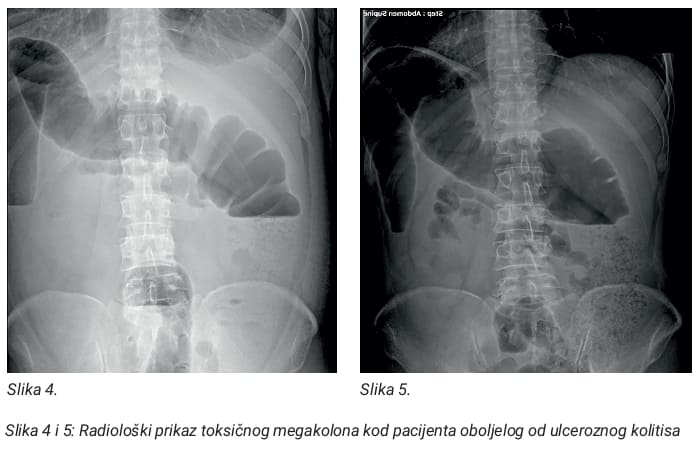

Ulcerozni kolitis i Crohnova bolest imaju neke zajedničke komplikacije, a druge su specifične za svaku bolest. Jedna od najčešćih komplikacija koja se može razviti i u Crohnovoj bolesti i u ulceroznom kolitisu je rak debelog crijeva. Određena stanja, uključujući artritis, lezije kože i upala oka, koja se naziva uveitis, se može pojaviti tokom IBD, te njih opisujemo kao ekstraintestinalne manifestacije osnovne bolesti. Komplikacije specifične za Crohnovu bolest mogu uključivati: nastanak stenoze, pothranjenost, razvoj fistule (perianalne i rektovaginalne), analne fisure, anemija itd. Komplikacije specifične za ulcerozni kolitis su toksični megakolon, perforacija kolona itd.

6. Slike 1-5 su napravljene od strane autora u ustanovi u kojoj je zaposlen i dozvoljene su za korištenje za potrebe objave edukativnog članka